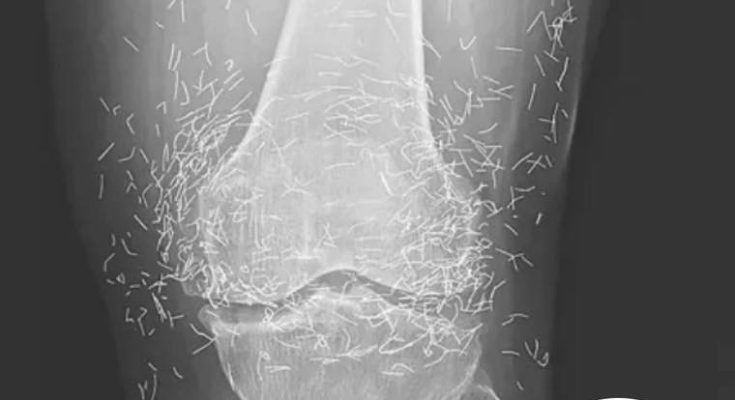

A routine X-ray revealed an unexpected surprise when doctors examined the knees of a 65-year-old woman suffering from severe joint pain. What they found was nothing short of astonishing — hundreds of tiny gold needles embedded deep in her tissue.

A X-ray of the patient’s knee showing acupuncture needles embedded in the tissue, Photo Credit: Reddit

As for the South Korean woman, her case was recently documented in the New England Journal of Medicine. While the needles may have been intended to help, her X-rays tell a cautionary tale about the potential risks of extreme alternative therapies.